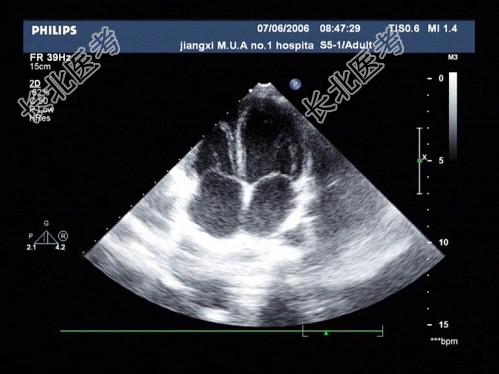

- 单项选择题如图切面称为何种超声心动图切面 ( )

A、心尖四腔

B、左室长轴

C、心尖短轴

D、心尖二腔

E、大动脉短轴